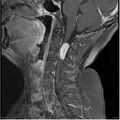

Compared to intracranial meningiomas, spinal lesions are less common (approximately 1.2–12.7% of all meningiomas). Spinal meningiomas are most commonly diagnosed in patients between 60 and 80 years of age. They grow slowly, are usually solitary, benign, lateral expansion within the subarachnoid space is typical, they are well demarcated, non-invasive.

In both intracranial and spinal meningiomas, there is considerable gender predominance in women (2: 1 ratio [women: men] in intracranial meningiomas, 4: 1 in spinal meningomes). This is associated with the association of meningiomas with breast cancer, as well as a greater likelihood of tumor growth during pregnancy. This is because meningiomas usually contain esterogenic and progesterone receptors.[29][30][31][32]

The most common localization of spinal meningiomas is the thoracic segment of the spine, followed by the cervical area. Spinal cord functions are compensated for a long time, but decompensation can take place quickly and this can lead to an acute worsening of the patient's condition (most often paraplegia). [33][34][35] First definition of ecotoxicology (1969): René Truhaut: the study of the adverse effects of chemicals with the aim of protecting natural species and communities. Rachel Carson (1962): the memoir The Silent Spring highlights the use of pesticides , especially DDT and other agrochemicals. The book led to the establishment of the US Environmental Protection Agency (EPA) in the USA. Introduction of methods describing the toxic effects of human-produced substances on the environment and the organisms contained therein. Systematic implementation of fish toxicity testing methods. In addition to direct toxic effects, the effects of bioconcentration and bioaccumulation are studied – increases in the concentration of foreign substances in the tissues of organisms as a result of exposure from the environment.